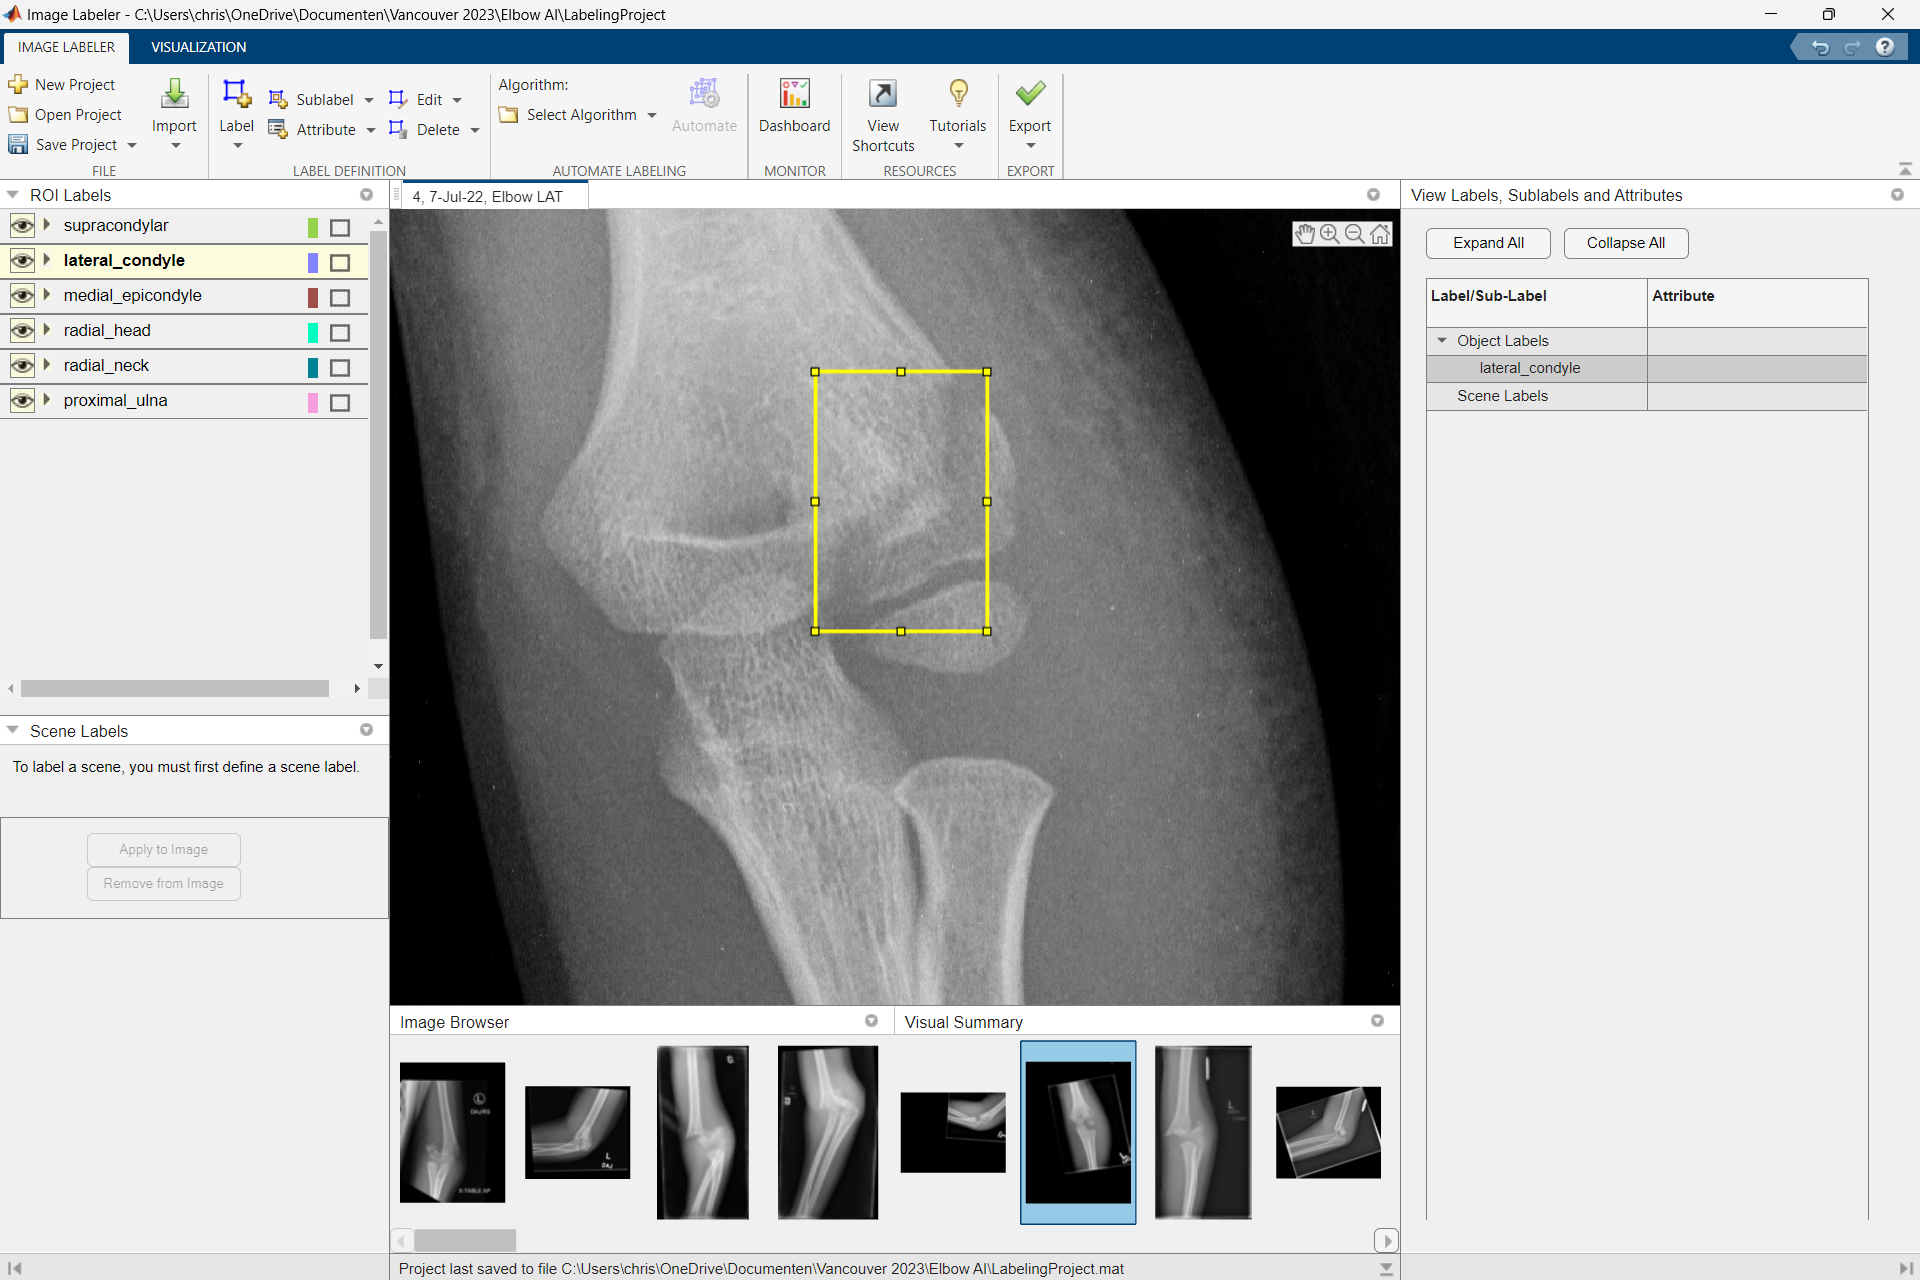

Pediatric orthopedics

In our department research of the musculoskeletal system is done on several topics concerning congenital diseases, traumatic injury and growth- or developmental disorders.

In pediatric orthopedics diseases are treated concerning the musculoskeletal system. This includes congenital diseases, traumatic injury, growth and developmental disorders.